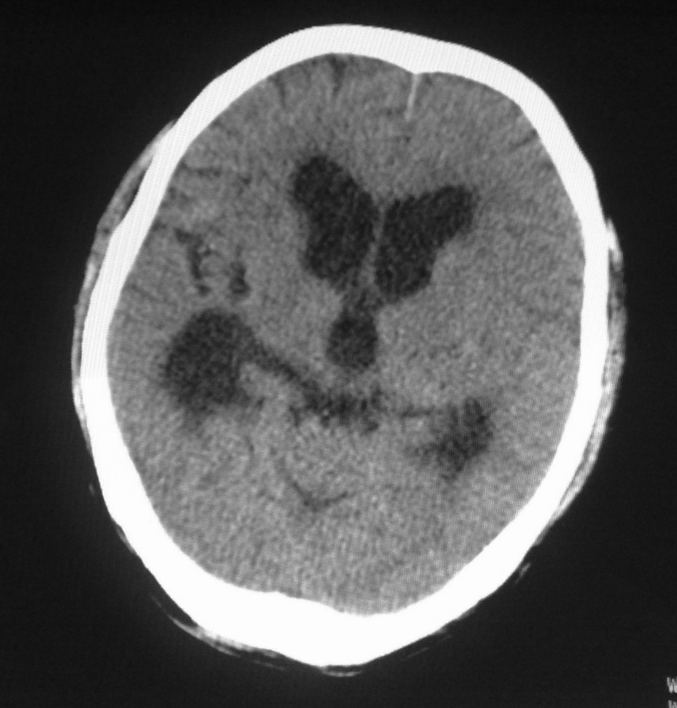

标题: CT24862:男,61岁,发热,有脑出血病史。 [打印本页]

男,61岁,发热,有脑出血病史。

右侧基底节,放射冠软化灶,胼胝体发育不良 脑积水原因待查。

右侧基底节及放射冠软化灶,脑积水,四脑室显示不清,导水管梗阻?建议mri!

梗阻性脑积水,出血后粘连所致

1)右侧基底节区、右侧放射冠及右侧丘脑软化灶。2)脑积水。